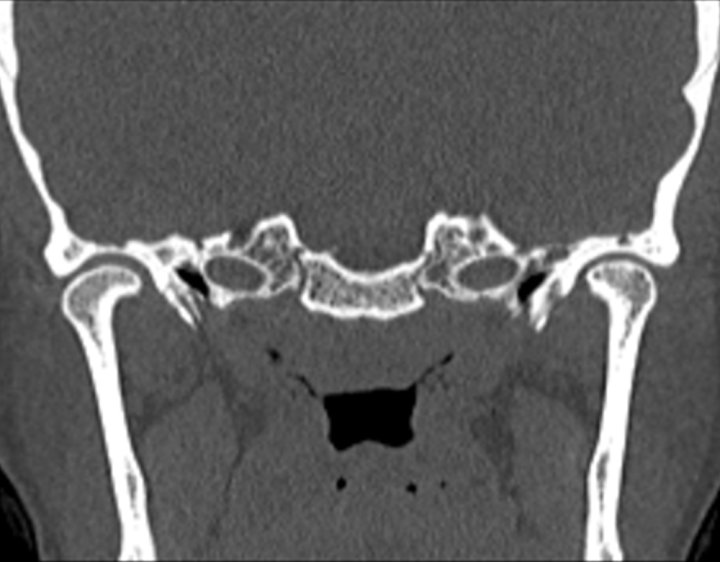

Click any image for labels.